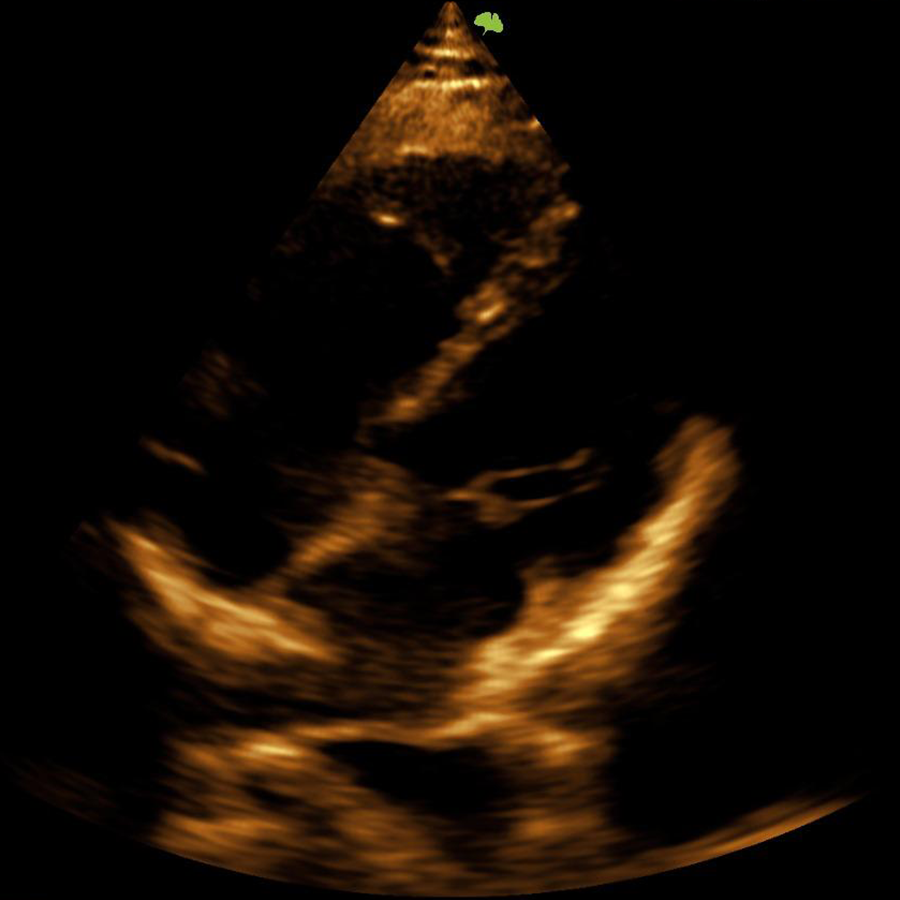

Cardiología

- CW

- ECG

- TVI

- TD

- Eco-Estrés

- Strain

- EF Automática

- PWV

- M Doppler Color

- M Doppler Tisular

- MAM

- Auto EF